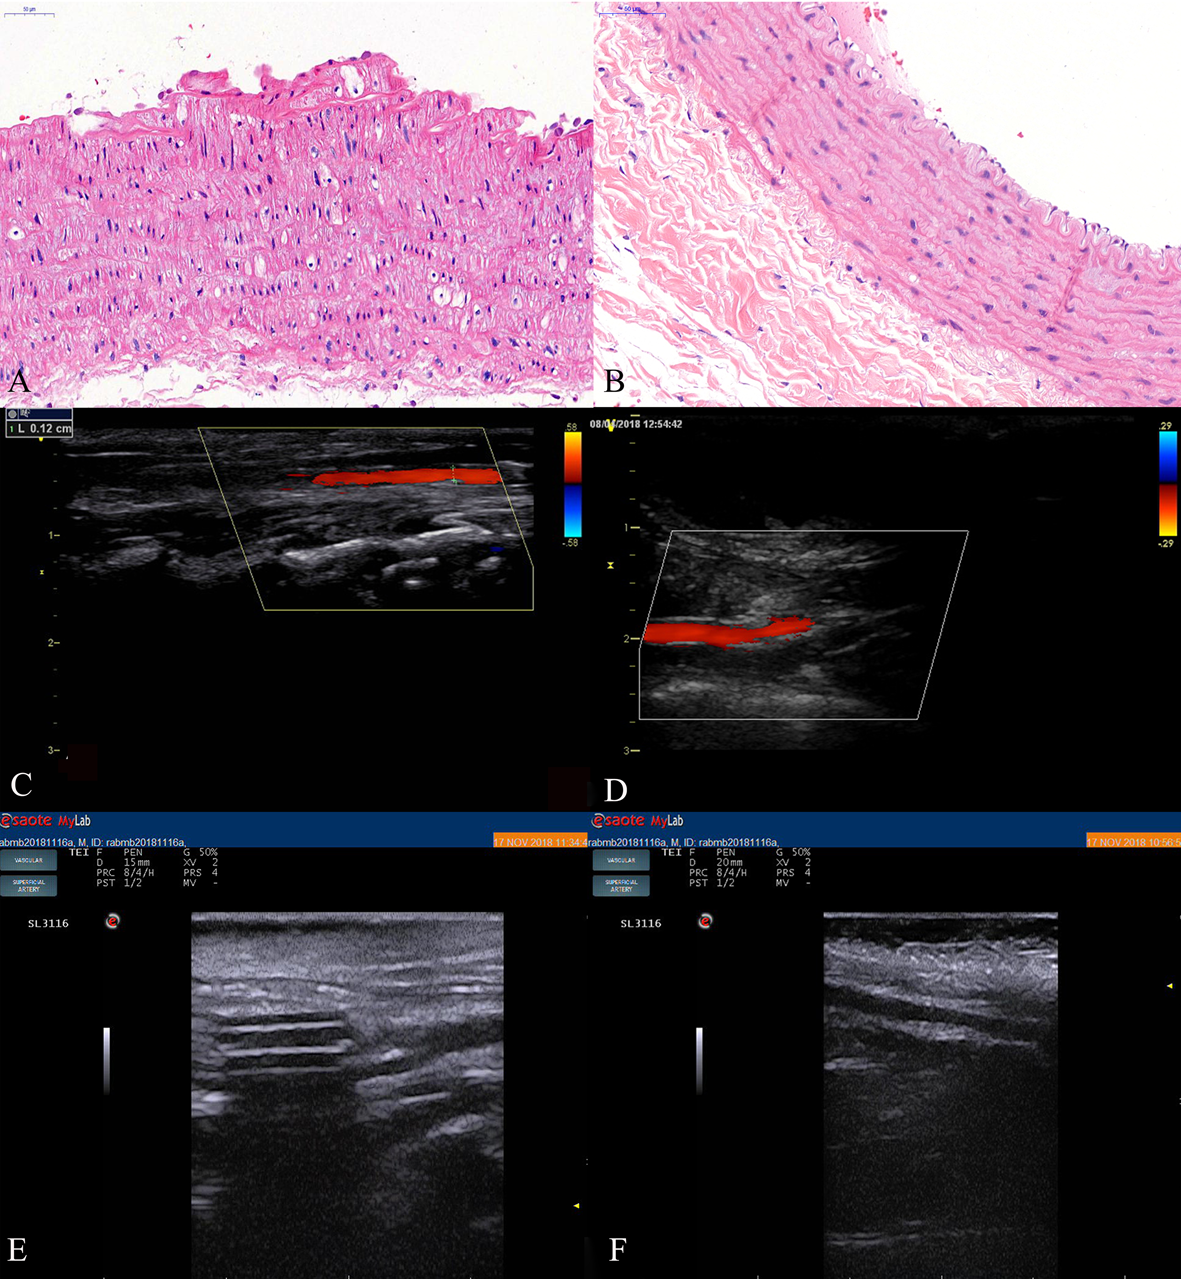

After the injection of the ultrasound contrast agent, contrast agent signal was observed in the carotid lumen at 3 seconds after injection in the four groups except for the control group (Fig. 6). The arrival time inside the plaque was later than that of the the carotid lumen, and strengthening began at the plaque base and gradually progressed to the more internal portions or short linear strengthening, which was predominantly level II or level III. After the enhancement lasted for several minutes, the enhancement effect at the plaque gradually weakened, and the contrast agent gradually cleared.

Fig. 6.Rabbit carotid artery contrast-enhanced ultrasound. (A) Image showing the anti-VCAM-1 nanometer contrast agent group with short linear enhancement in the plaque. (B) Image showing the nanoscale contrast agent group with dot enhancement in the plaques. (C) Anti-VCAM-1 sonovi group. (D) SonoVue group; dot enhancement was observed in all plaques. (E) Control group; no contrast agent sonogram is observed in the lumen.

There was a statistically significant difference in the arrival time of the

plaques between group A and group B (p